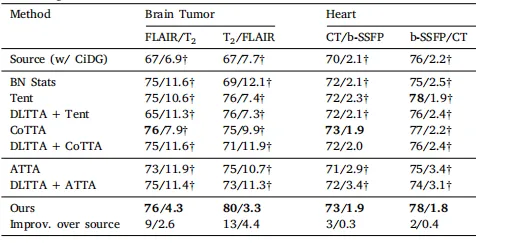

Table 3Quantitative evaluation of benchmarked methods (with CiDG source model) on the brain tumor and heart substructure segmentation tasks. The same source model (CiDG)was used by all benchmarked methods. Results are shown in form of Dice (%)/ASSD(mm). † denotes statistical significance between the Dice/ASSD score of a methodand that of our method (𝑝 < 0.05). Source and target domains were presented as source/target in the second row. Best results are in bold

表3 基准方法(使用CiDG源模型)在脑肿瘤和心脏子结构分割任务中的定量评估。 所有基准方法均使用相同的源模型(CiDG)。结果以Dice(%)/ASSD(mm)的形式表示。† 表示某方法的Dice/ASSD得分与我们方法的得分之间具有统计显著性(𝑝 < 0.05)。源域和目标域在第二行以"源域/目标域"形式呈现。粗体表示最佳结果。